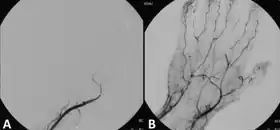

Those unsuitable for surgery may receive thrombolytics. In the past, streptokinase was the main thrombolytic chemical. More recently, drugs such as tissue plasminogen activator, urokinase, and anistreplase have been used in their place. Mechanical methods of injecting the thrombolytic compounds have improved with the introduction of pulsed spray catheters—which allow for a greater opportunity for patients to avoid surgery.[19][20] Pharmacological thrombolysis requires a catheter to be inserted into the affected area, attached to the catheter is often a wire with holes to allow for a wider dispersal area of the thrombolytic agent. These agents lyse the ischemia-causing thrombus quickly and effectively.[21] However, the efficacy of thrombolytic treatment is limited by hemorrhagic complications. Plasma fibrinogen level has been proposed as a predictor of these hemorrhagic complications. However, based on a systematic review of the available literature until January 2016, the predictive value of plasma is unproven.[22]

Mechanical thrombolysis

Another type of thrombolysis disrupts the clot mechanically using either saline jets or, more recently, ultrasound waves. Saline jets dislodge the clot using the Bernoulli effect. Ultrasound waves, emitted at low frequency, create a physical fragmentation of the thrombus.[23]